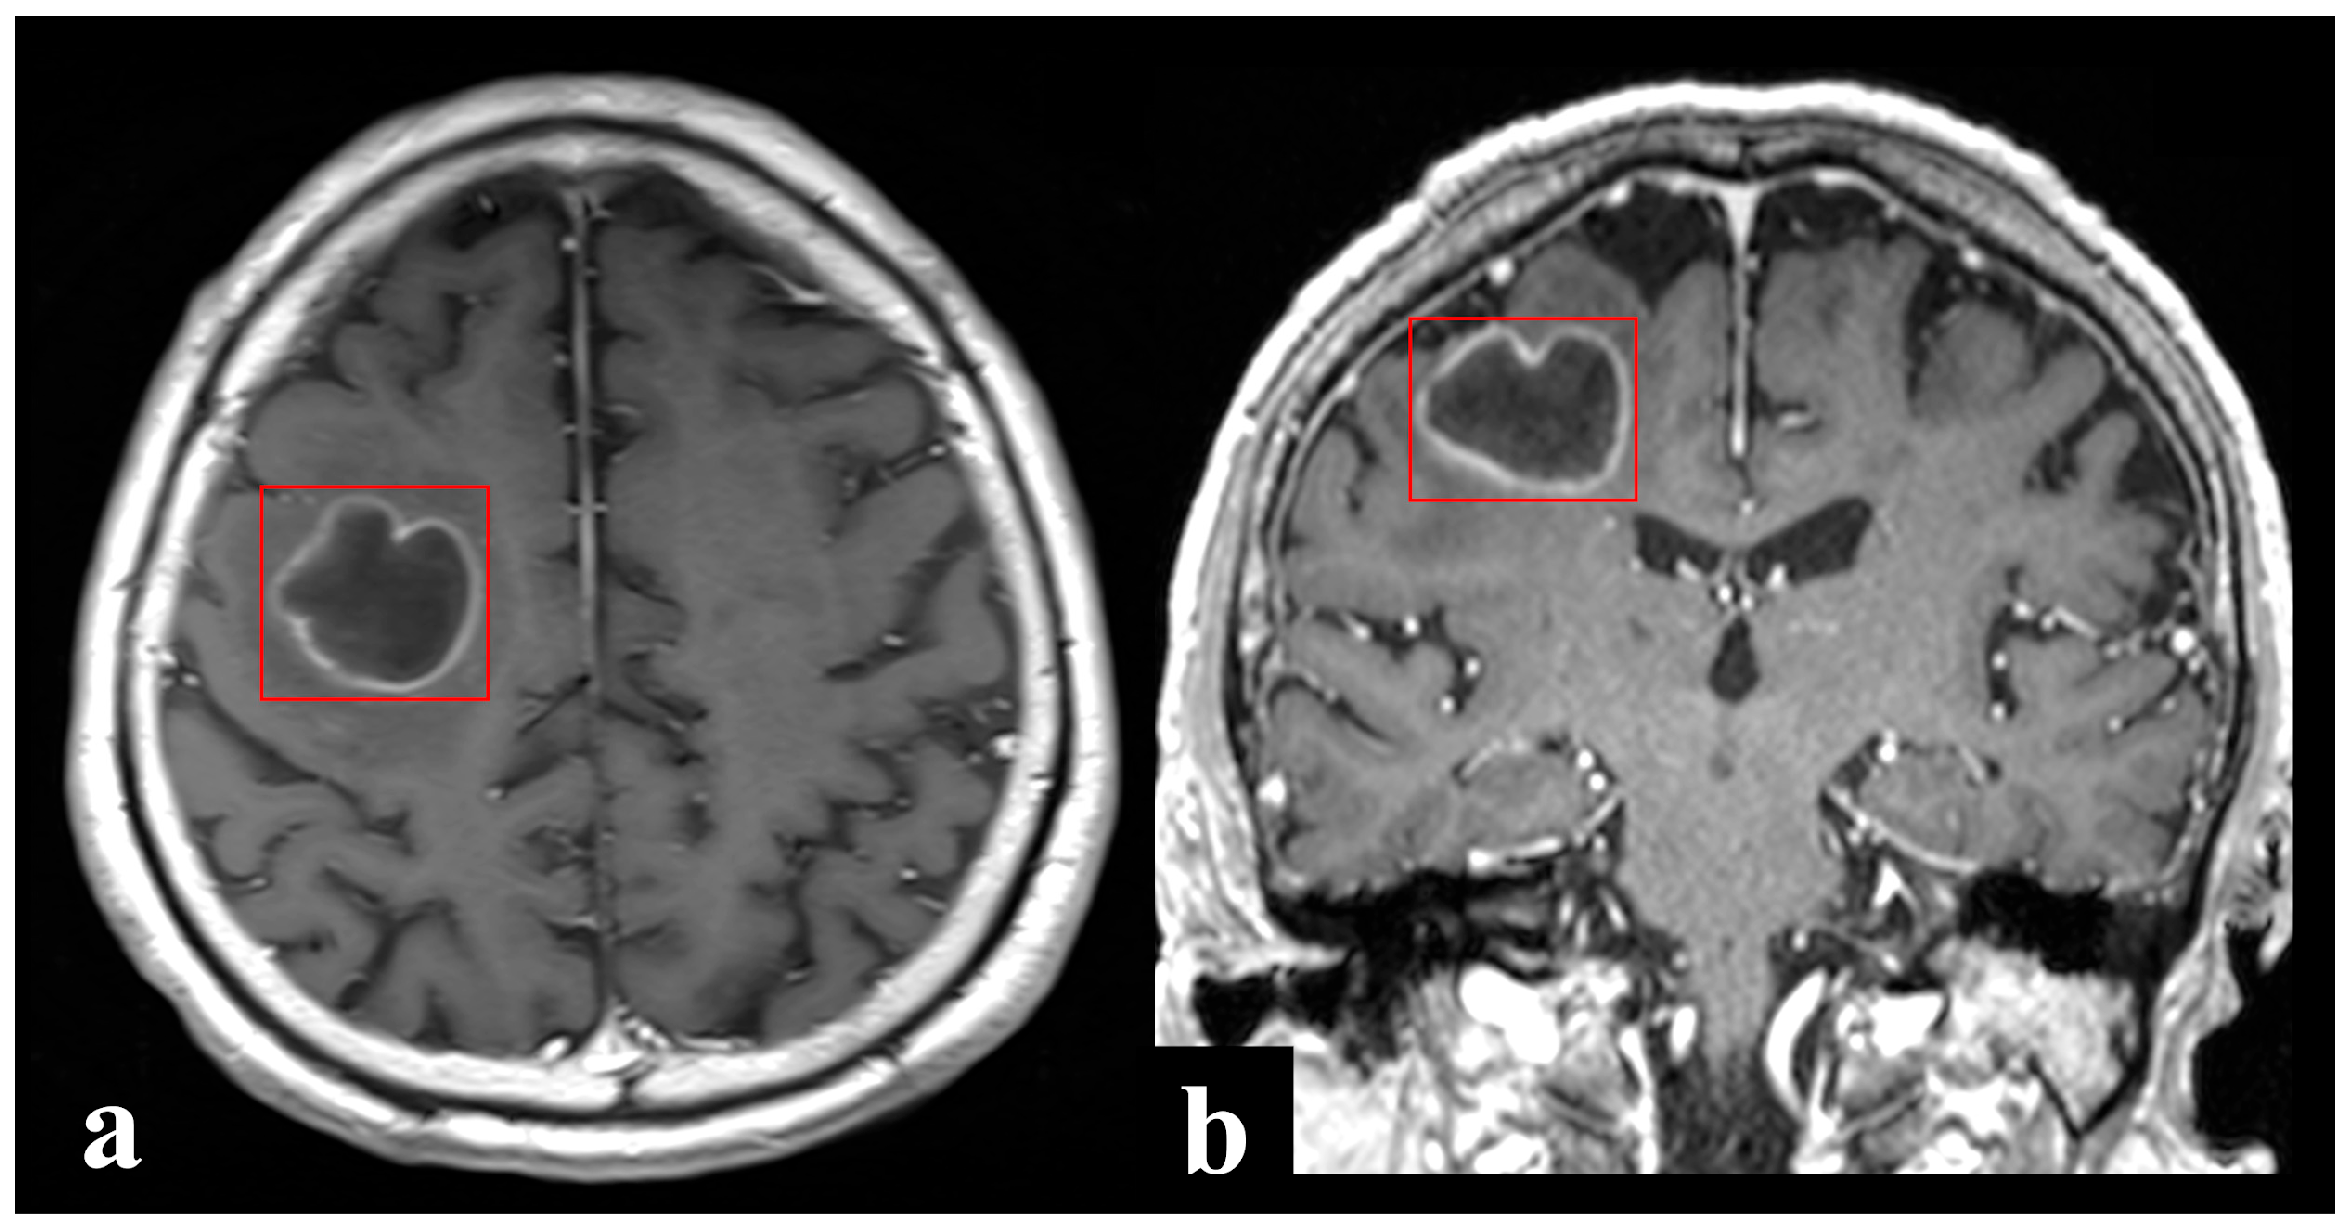

2.2. Image Annotation and Pre-Processing

The REBLs were manually annotated by a research assistant and final-year medical students using the XNAT software (v1.8.8) under the direct supervision of board-certified neuroradiologists. XNAT is an open source imaging informatics platform that facilitates common management, productivity, and quality assurance tasks in imaging-based research. Each discrete REBL identified on 3D scans was annotated and sought for annotation on 2D axial scans (Figure 2). Bounding box annotations were made on each contiguous section to include the entire enhancing margins of the REBL. In this way, surrounding imaging context (vasogenic edema or non-enhancing lesional margins beyond the ring enhancement, e.g., in infiltrative primary brain tumors) which may contribute meaningfully to decision-making were also included, albeit incompletely. Satellite and multilocular lesions which could not be separated from the primary REBL/dominant lobule were included in the same bounding box. Related nodular or solid enhancing lesions (without central necrosis or cystic change) and meningeal involvement, when present, were also annotated. Detailed step-by-step annotation protocol is provided in Supplementary Data S2. All T1+C scans were uniformly resampled to 2mm isotropic voxels before radiomic feature extraction from the annotated bounding boxes.

Figure 2. Depiction of bound box annotations of a right frontal ring-enhancing pyogenic brain abscess on (a) axial 2D and (b) coronal 3D post-contrast T1-weighted MRI images. [original image].